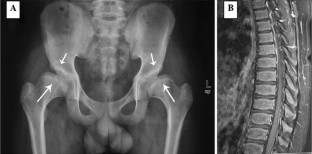

Fig. 1